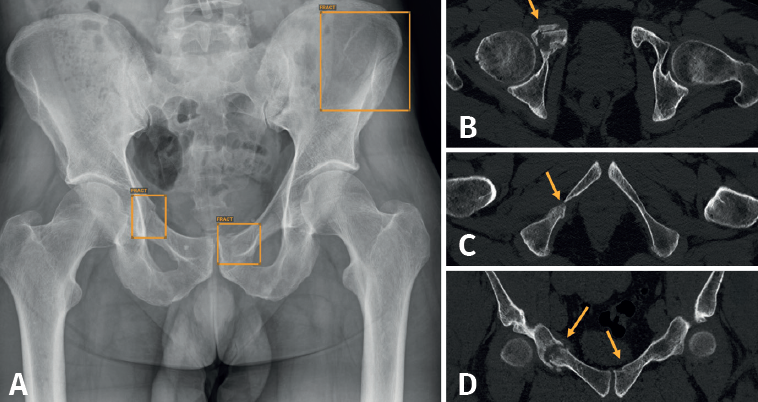

En nuestro caso, decidimos que toda radiografía que llega al PACS se enviara directamente y de manera automática al análisis por la IA, evitando un uso “a demanda” del médico, para favorecer su consulta. El resultado del análisis es devuelto al PACS en un plazo de 1-2 minutos, poniéndolo a disposición del personal médico para su valoración. Los resultados se presentan de manera clara y fácil de interpretar, en 3 niveles: negativo, dudoso o positivo (Figura 2); los dos últimos señalan con un recuadro en la radiografía la imagen de fractura. La diferencia entre un resultado positivo (recuadro con línea continua) y uno dudoso (recuadro con línea discontinua) estriba en un nivel de confianza alto o intermedio para la lesión detectada. Esta solución de IA detecta fracturas en todas las localizaciones anatómicas excepto el cráneo y la columna cervical, y, además, identifica derrames articulares, luxaciones y lesiones óseas. Como control de calidad, se indica el número de imágenes recibidas y el número de imágenes analizadas.

Aunque no hemos realizado un estudio de sensibilidad y especificidad por la complejidad que entraña en la práctica asistencial, consideramos que los resultados son satisfactorios, en línea con lo publicado en la literatura científica. Destacamos la eficacia del algoritmo en la detección de pequeñas fracturas arrancamiento (Figura 3), fracturas de radio distal y proximal (Figura 4), y fracturas múltiples (Figura 5).